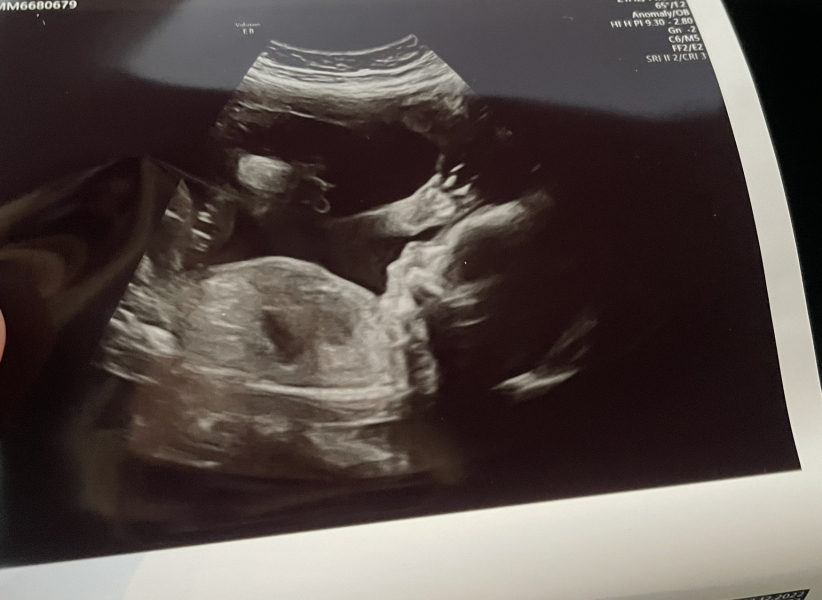

Had my 20 week scan yesterday and can't believe it!!! It's a girl ✨✨💕

Honestly every single person I know, had said BOY. Not one person ever said girl. So I was convinced it was a boy. I'm so shocked!!!! But so happy everything looked all normal and healthy! What a relief. Hopefully the rest of the pregnancy continues to be a success! Baby girl waving 😂

@xalexandra no way congratulations! How exciting!!!

that’s a gorgeous scan, so glad it all went okay! Xx

Oh my goodness she’s waving as well! Congratulations 💜 beautiful!! Mines booked for next Thursday 🤞 xx